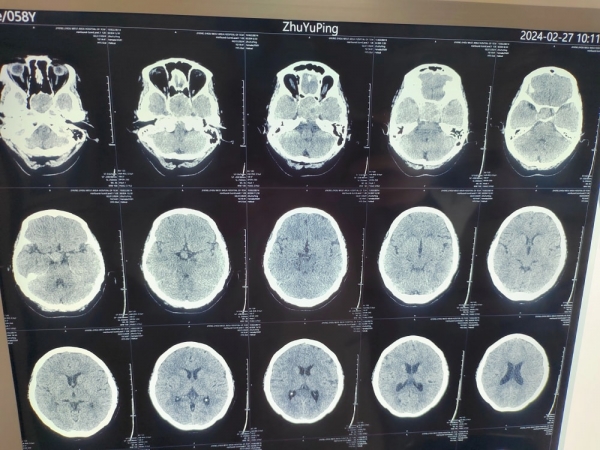

詢問朱大姐情況后,張院長為其進(jìn)行詳細(xì)檢查,CT檢查發(fā)現(xiàn)朱大姐鞍區(qū)瘤體變大,鞍區(qū)是人體大腦顱中窩中央部的位置,得了鞍區(qū)腫瘤會出現(xiàn)“視力降低、頭昏頭痛、內(nèi)分泌異?!钡痊F(xiàn)象,手術(shù)是解決腦部腫瘤的最佳方式。